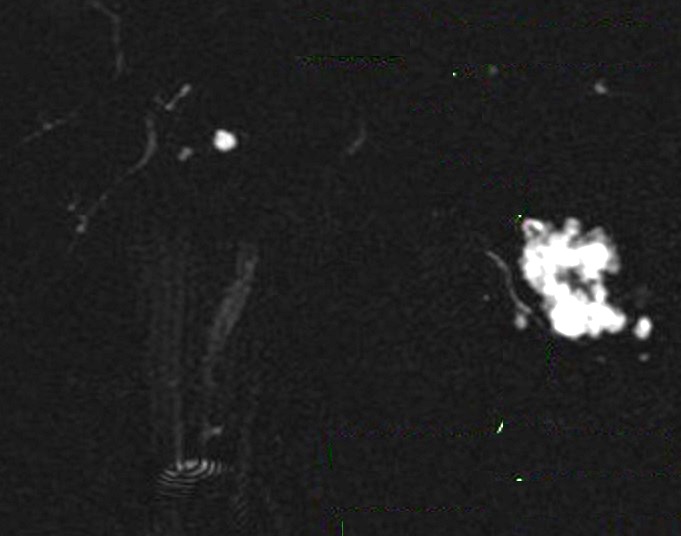

Image radiologique Wirsungo-

cholangio IRM d'une cystadenome sereux multikystique

du pancreas . N'a pas de communication canalaire du

kyste |